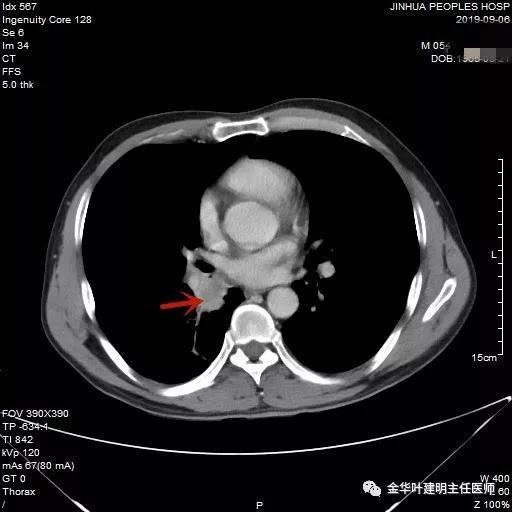

可见右中间支气管开口处新生物,堵塞管腔,明显是肿瘤,但因当时服用波立维与阿斯匹林双抗治疗,停的时间还不够,所以没有活检,而刷检没找到癌细胞。请我会诊时,我看了李某的胸部CT增强:

上图示中间支气管起始处似乎还算正常

上图示中间支气管起始处以下3毫米处已经管壁增厚异常

上图示肿瘤堵塞管腔

上面各图示肿瘤位于肺门部,堵塞下叶及中间支气管

我们仔细看了增强CT,纵隔未见确切疑似转移的肿大淋巴结,这样的情况下,是不是再次气管镜活检,还是直接可以手术?当然从原则上来讲,应该再重新纤支镜检查,再活检以取得病理确诊后,再行手术。但个人以为,从影像及气管镜所见来讲,临床诊断已经可以确定为肺癌,而且中央型的以鳞癌为多见,当然也有的会是小细胞癌,不过小细胞癌一般很早就会有纵隔淋巴结转移,如果患者及家属理解,我认为从减少痛苦、节约经费、节省时间等方面考虑,直接手术也基本不会错的。当然所有的利弊与可能都要如实与患者及家属沟通,并征求他们的意见,最终李某及家属选择不再重新纤支镜检查与活检,要求直接手术。